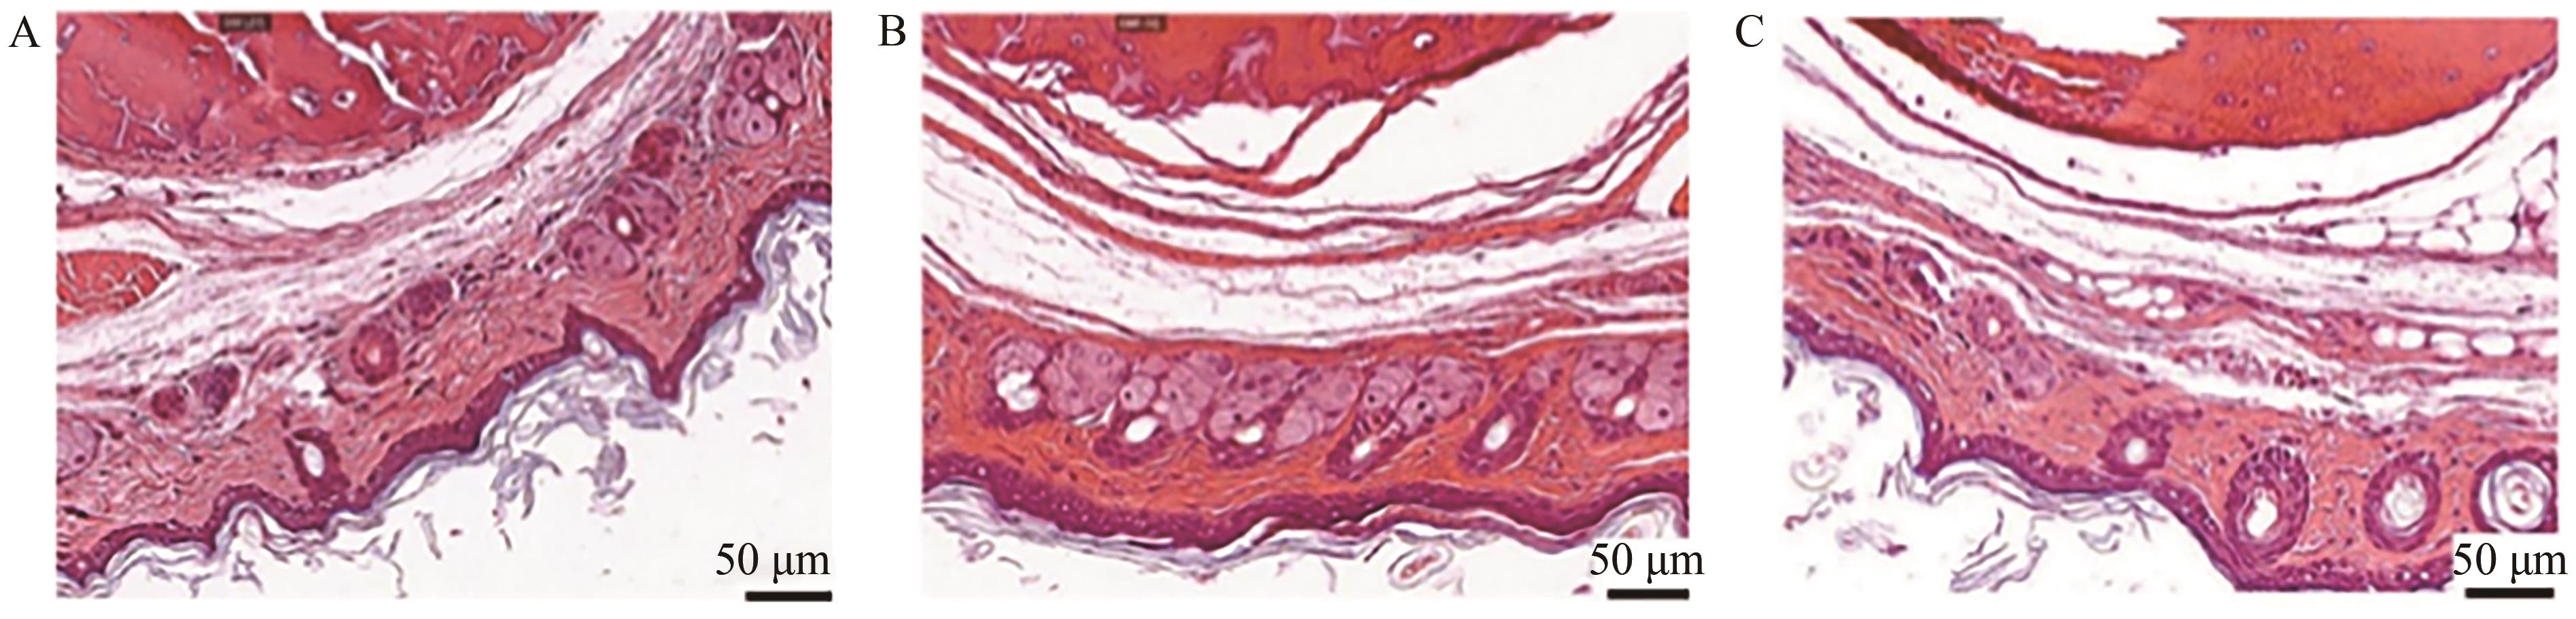

Table 6 Skin irritation scale (erythema) for different subjects

Table 7 Skin irritation rating scale (edema) for different subjects

| Saline | Blank preparation | BUP-ME-GEL | |

| Score | 0 | 0 | 0.25 |

| Stimulus intensity | Non-irritating | Non-irritating | Non-irritating |

Table 8 Skin irritation evaluation results for different subjects